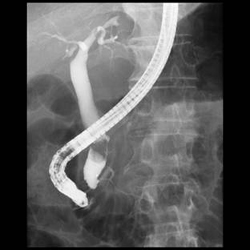

■Ultimaxi:キヤノンメディカルシステムズ

当院では2020年12月に最新型のX線TV装置を導入しました。これにより画質が格段に向上し、精度の高い消化管(胃・大腸)造影検査が行えるようになりました。

更に気管支鏡検査や内視鏡的胆管膵管造影検査(ERCP)、消化器、泌尿器、整形領域などの処置も従来

より安全かつ効率的に行えることで、検査時間の短縮、放射線被ばくの軽減(旧装置の最大65%減!)も期待できます。

また車椅子やストレッチャーから装置への体位移動がよりスムーズに行うことが可能で、患者さんの負担も軽減されました。